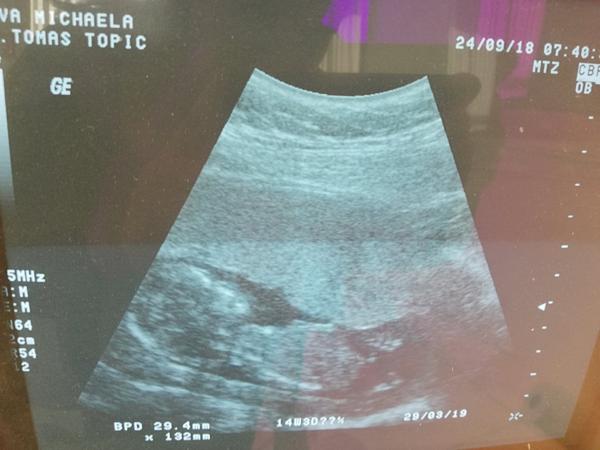

Ahoj holky, čekáme s přítelem první miminko.... Moc se na něj těšíme. Pohlaví nám pan doktor neurčí, musí počkat na další screening ve druhém trimestru. Ale prakticky všichni z rodiny vidí na fotkách z ultrazvuku kluka, co myslíte, může to být kluk??

@michaelah94 ten výběžek je pohlavní hrbolek - ten mají všechny mimina v prvním trim stejný, na konci prvního trim. 13-14 tt jde velmi dobře poznat zda je to on či ona - hrbolek je stále u obou ale sklonem se liší.

vy jste dle fotky 12+0 tady by to tedy bylo věštění z koule.. je to malé.. to co vypadá jako pindík totiž úplně v pohodě může být klitoris

@michaelah94 tak dle prvni fotky by to dle pohlavniho hrbolku mela byt holka....takto jsem to ted mela i ja a bylo mi receno..ze zo vypada na holcicku a na potvrzeni si musim take pockat. Ale dr.mi rikala ze kluci maji pohlavni hrbolek smerem nahoru. Tak jak je to krasne videt na fotkach...co tady dala odkaz verys.